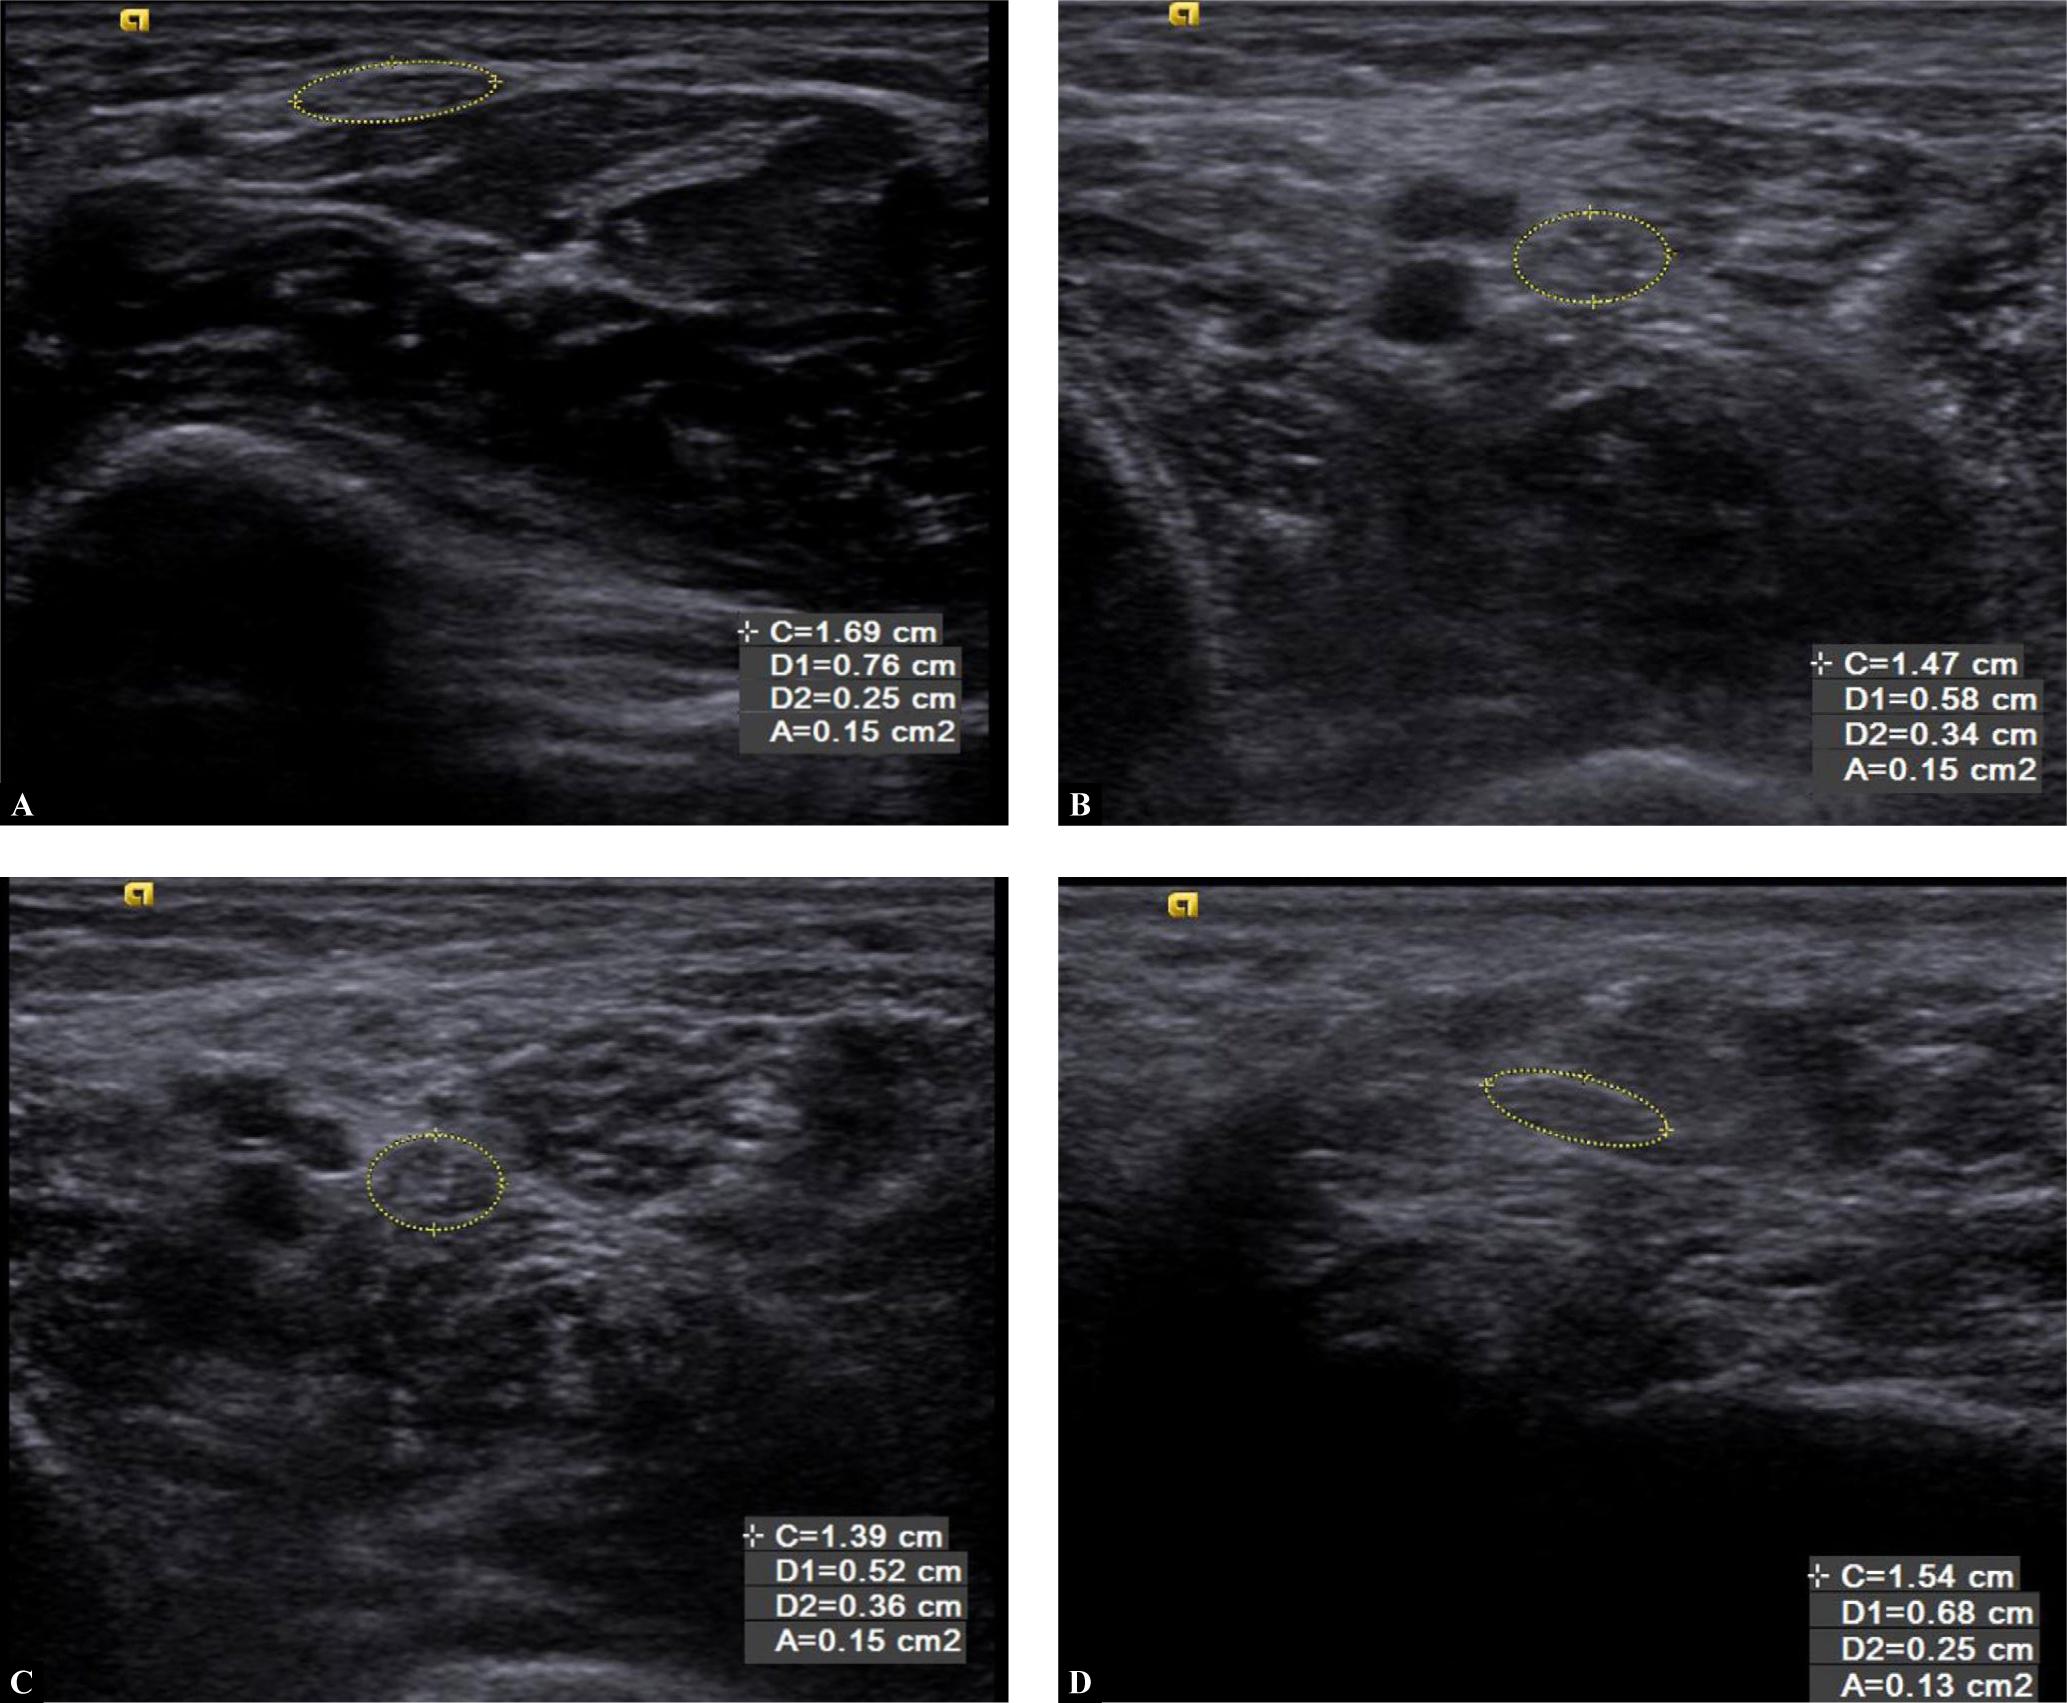

Fig. 1.

Transverse grey-scale ultrasound showing: A. Thickening of median nerve in a 65-year-old male patient diagnosed with T2DM 10 years previously. The patient had pain in both lower limbs. His HbA1c was 9% and his random blood sugar value was 400 mg/dl. It shows mean cross-sectional area of 15 mm2. B. Thickening of tibial nerve at 1 cm proximal to medial malleolus (in the same patient). C. Thickening of tibial nerve (in the same patient) at 3 cm proximal to medial malleolus. D. Thickening of tibial nerve (in the same patient) at 5 cm proximal to medial malleolus

We measured the CSA of the median nerve at 5 cm proximal to the wrist (MN 5 cm) and the tibial nerve at 1, 3 and 5 cm (TN 1 cm, TN 3 cm, TN 5 cm) proximal to the medial malleolus, revealing a positive relationship between the duration of diabetes and the CSA of these nerves, i.e. as the duration of diabetes increased, the nerve thickness also increased. There was a positive correlation between the CSA of the two nerves and HbA1c levels, duration of diabetes, RBS levels, and monofilament examination (Fig. 1A–1D). Subjects who had good glycaemic control and a shorter duration of diabetes showed no significant thickening of the nerves (Fig. 2A–2D).